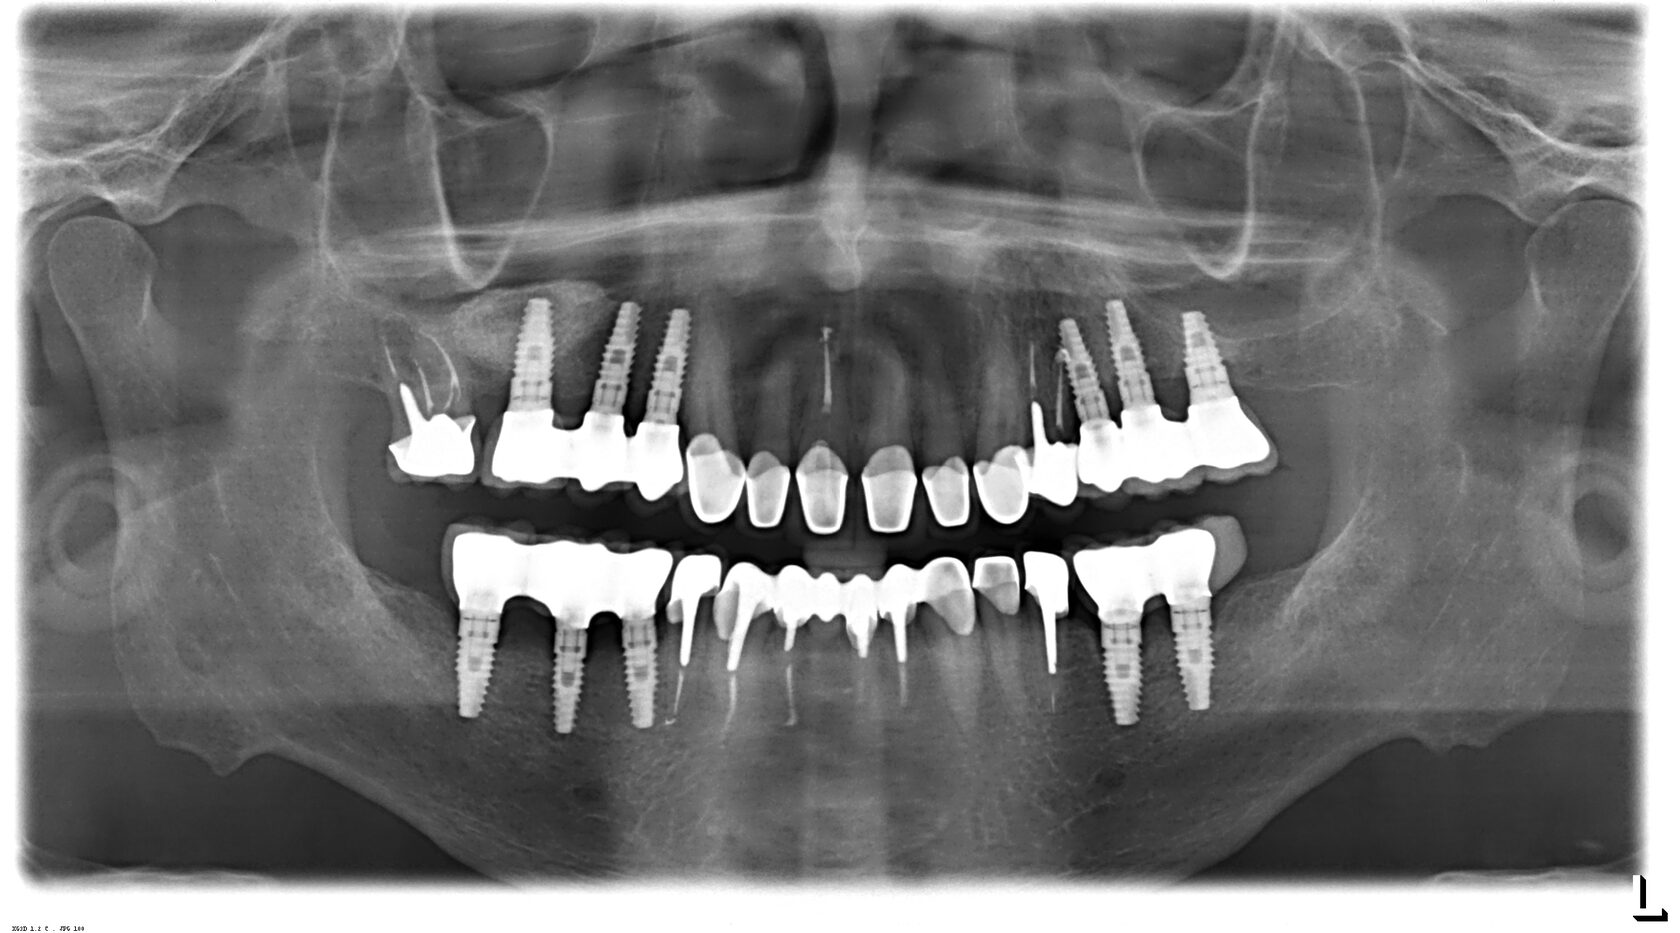

Панорамный снимок. Этот метод рентгеновского исследования зубов делает возможным получение снимка с полным изображением челюсти и всех зубов пациента. Благодаря применению цифровых технологий и высококачественной пленки изображение получается чрезвычайно четким и детальным. Это делает процедуру важным этапом диагностики перед удалением зубов и не только.